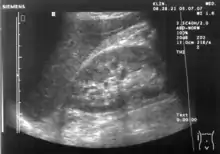

Abdominal ultrasonography (also called abdominal ultrasound imaging or abdominal sonography) is a form of medical ultrasonography (medical application of ultrasound technology) to visualise abdominal anatomical structures. It uses transmission and reflection of ultrasound waves to visualise internal organs through the abdominal wall (with the help of gel, which helps transmission of the sound waves). For this reason, the procedure is also called a transabdominal ultrasound, in contrast to endoscopic ultrasound, the latter combining ultrasound with endoscopy through visualize internal structures from within hollow organs.

Abdominal ultrasound can be used to diagnose abnormalities in various internal organs, such as the kidneys,[1] liver, gallbladder, pancreas, spleen and abdominal aorta. If Doppler ultrasonography is added, the blood flow inside blood vessels can be evaluated as well (for example, to look for renal artery stenosis). It is commonly used to examine the uterus and fetus during pregnancy; this is called obstetric ultrasonography.[2][3]

Ultrasonography of the kidneys is essential in the diagnosis and management of kidney-related diseases. The kidneys are easily examined, and most pathological changes in the kidneys are distinguishable with ultrasound.[7]